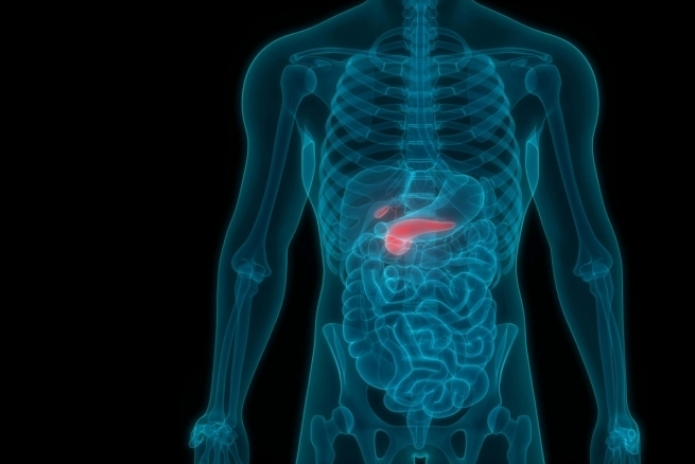

“당뇨로 진단받았는데 알고보니 췌장암이었다”는 최근 사례와 관련해, 의료계에서 경고하는 췌장암 초기·잠복 증상들을 정리해드릴게요. 당뇨가 늘 있다고 무조건 췌장암은 아니지만, 아래 증상들 중 하나 이상 있다면 주의해볼 필요가 있습니다.

- 일반적으로 췌장은 몸속 깊숙이 있고 초기 증상이 모호해서 ‘침묵의 장기’라 불림. Medical Times+1

🔍 췌장암 주의 신호들

아래의 증상들을 특히 당뇨병이 새로 생겼거나 기존 당뇨가 갑자기 잘 조절되지 않게 된 경우 주의 깊게 살펴야 함: